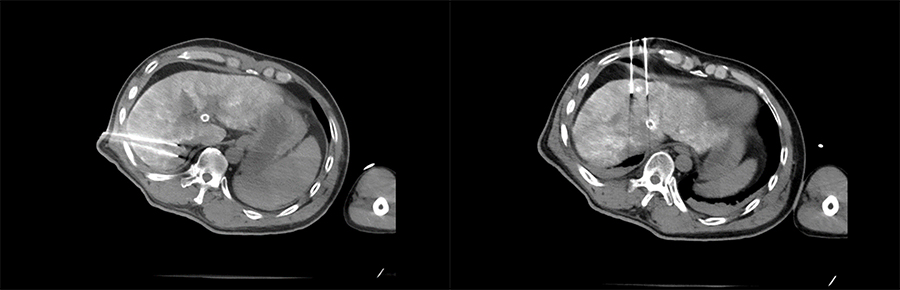

▲ 患者一手术过程

▲ 患者二手术过程